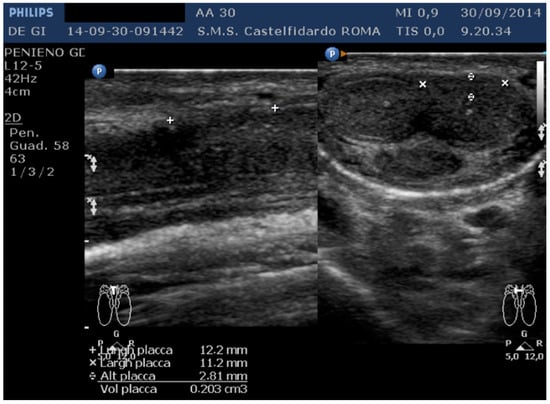

| 3 | 30 years | Left varicocele | Proximal third | (A) 12.2 × 11.2 × 2.81 mm volume = 203 mm3 (B) No plaque detected | (A) No penile deformation (B) No penile deformation | VAS score = 5 Pain disappeared after 4 months | 26 > 26 | 4 months | Orally: propolis 600 mg + bilberry 160 mg + silymarin 400 mg + ginkgo biloba 250 mg + vitamin E 800 IU/daily for 4 months + topically: diclofenac gel 4%/2× daily for 4 months Note: Penile injections not needed |